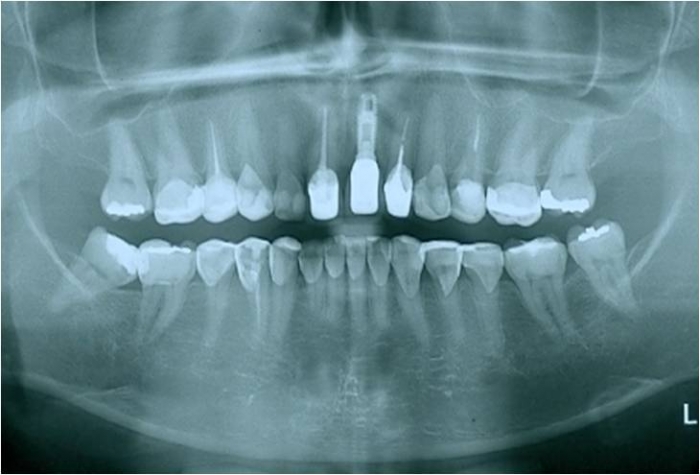

Raio X após a extração

Raio X com implante instalado